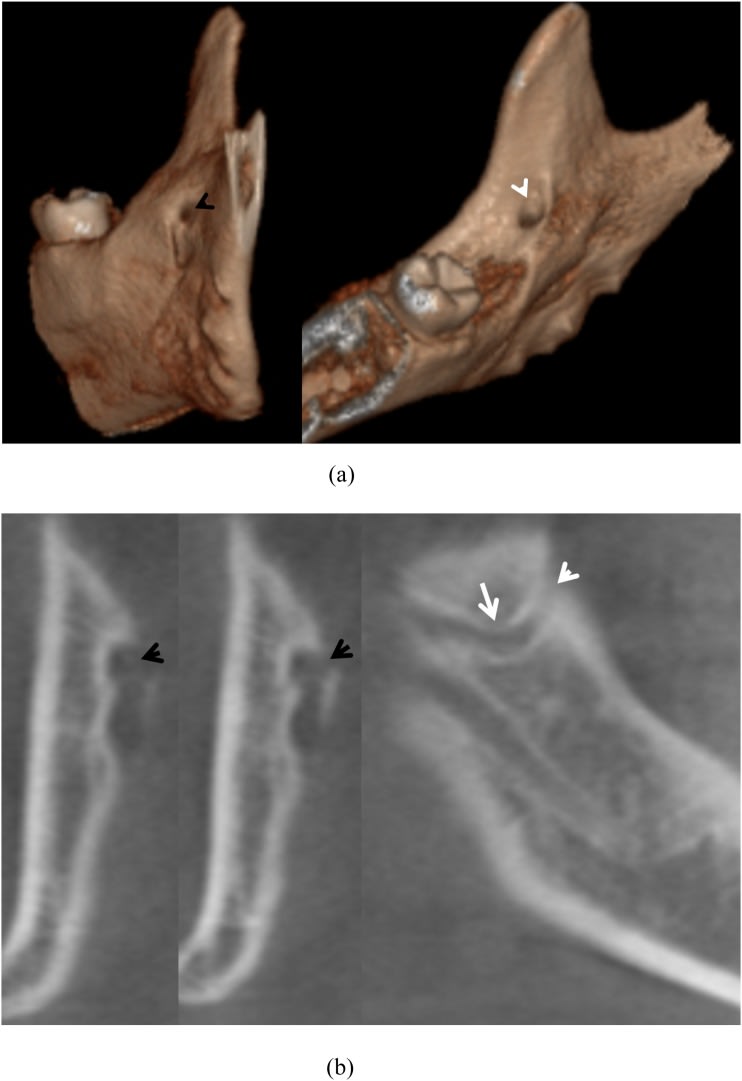

The anomalous canal between two accessory foramina on the mandibular ramus: the temporal crest canal.

They say in that article that some hypothesise that the long buccal nerve goes through the TCC. Others suggest branches of the mandibular nerve and vessels.